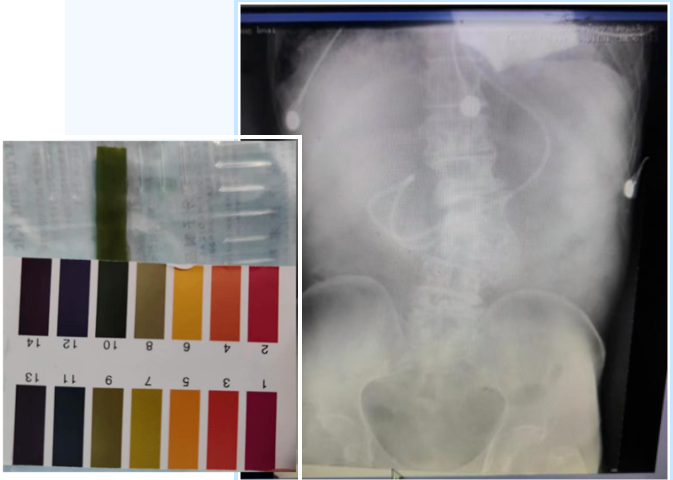

据悉,患者为81岁男性,以重症肺炎、肺栓塞、急性心肌梗死、休克入住重症医学科。由于患者处于意识模糊状态,且基础疾病多,病情危重。为保证肠内营养支持,重症医学科护理团队通过不断询证、学习和临床实践,巧妙利用患者呼吸时产生的起伏送入管道,在鼻空肠管进入一定长度后,再更换体位,使导管前端随重力作用穿过幽门,顺利到达空肠。术后经床旁X线和PH试法结果显示:鼻肠管尖端到达十二指肠升部,位置良好。床旁徒手盲插鼻空肠管术——开辟了重症患者性命攸关的营养通道。